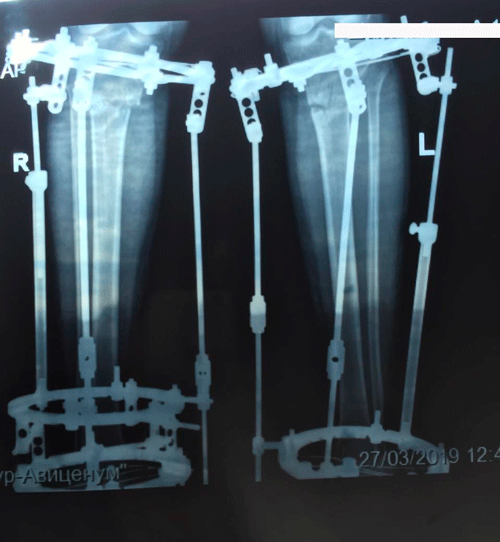

рентген в 60 дней

IMG_2081-27-03-19-08-55.gif

IMG_2083-27-03-19-08-55.gif

IMG_2084-27-03-19-08-55.gif